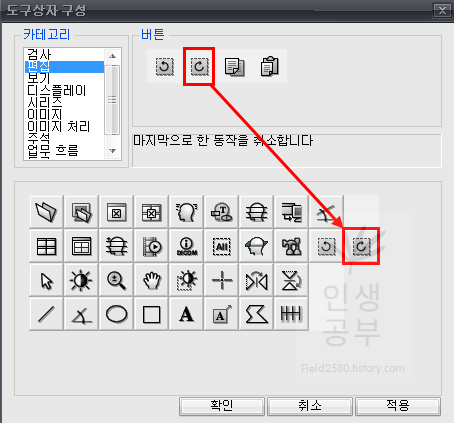

위와 같은 도구상자 구성 화면이 뜨게 됩니다. 아래에는 현재 사용중인 도구상자들이고 왼쪽 상단에는 도구상자에 넣을 수 있는 카테고리들이 있습니다. 카테고리칸 옆에는 버튼칸이 있고 아래 도구상자칸에 없는 메뉴들도 많이 있습니다. 아이콘에 마우스를 가져다 대면 간단한 설명이 나오니 필요하신 분들은 한번씩 다 확인해보시는 걸 추천해드립니다.

그 후에 저는 마지막으로 한 동작을 취소합니다 버튼과 이전에 취소한 동작을 다시 수행합니다 버튼을 많이 사용하기 때문에 추가했습니다. 카테고리에 있는 편집을 클릭해 주세요.

제일 앞에 있는 버튼이 마지막으로 한 동작을 취소합니다 버튼입니다. 버튼을 드래그해서 아래로 끌어다 줍니다.

마지막으로 한 동작을 취소합니다 버튼이 추가 된 것을 확인하실 수 있습니다.

그 후에 2번째 칸에 있는 이전에 취소한 동작을 다시 수행합니다 버튼을 추가해줍니다.

두 번째 버튼을 클릭하고 아래로 드래그해서 내려주면 아래 도구상자에 추가됩니다.참고로 위의 두 버튼은 단축키를 알아두시면 훨씬 편하게 사용하실 수 있습니다. 단축키가 익숙해지면 도구상자 메뉴에서 삭제해도 상관없습니다. 하지만 익숙해지기 전까지는 도구상자 메뉴에 넣어두시는 걸 추천해 드립니다.